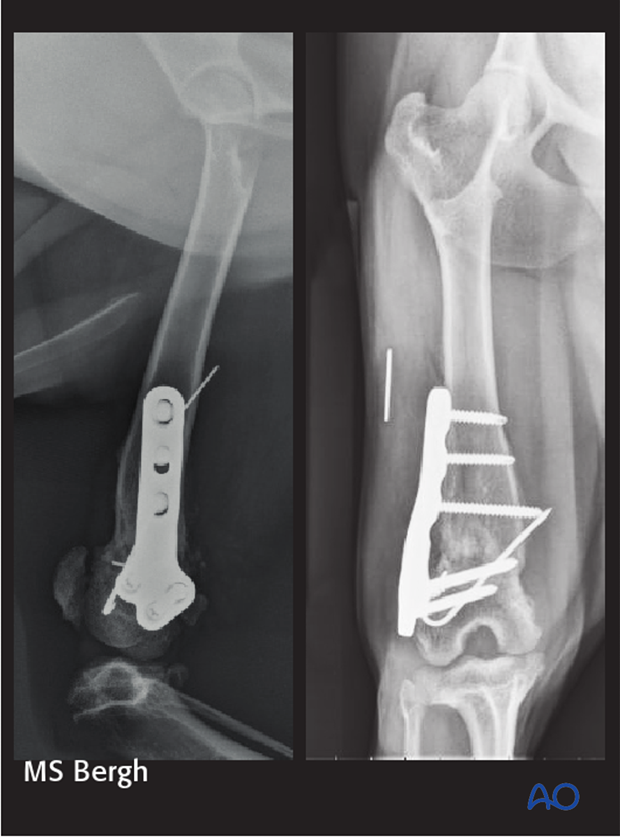

Images show a viable nonunion of a distal femoral fracture repaired with K-wires.

This fracture was revised using a locking compression plate, screws and a K-wire. Autogenous cancellous bone graft was placed at the fracture site.

Postoperative radiographs at 4 weeks show progressive bone union of the fracture. Clinical function was good.